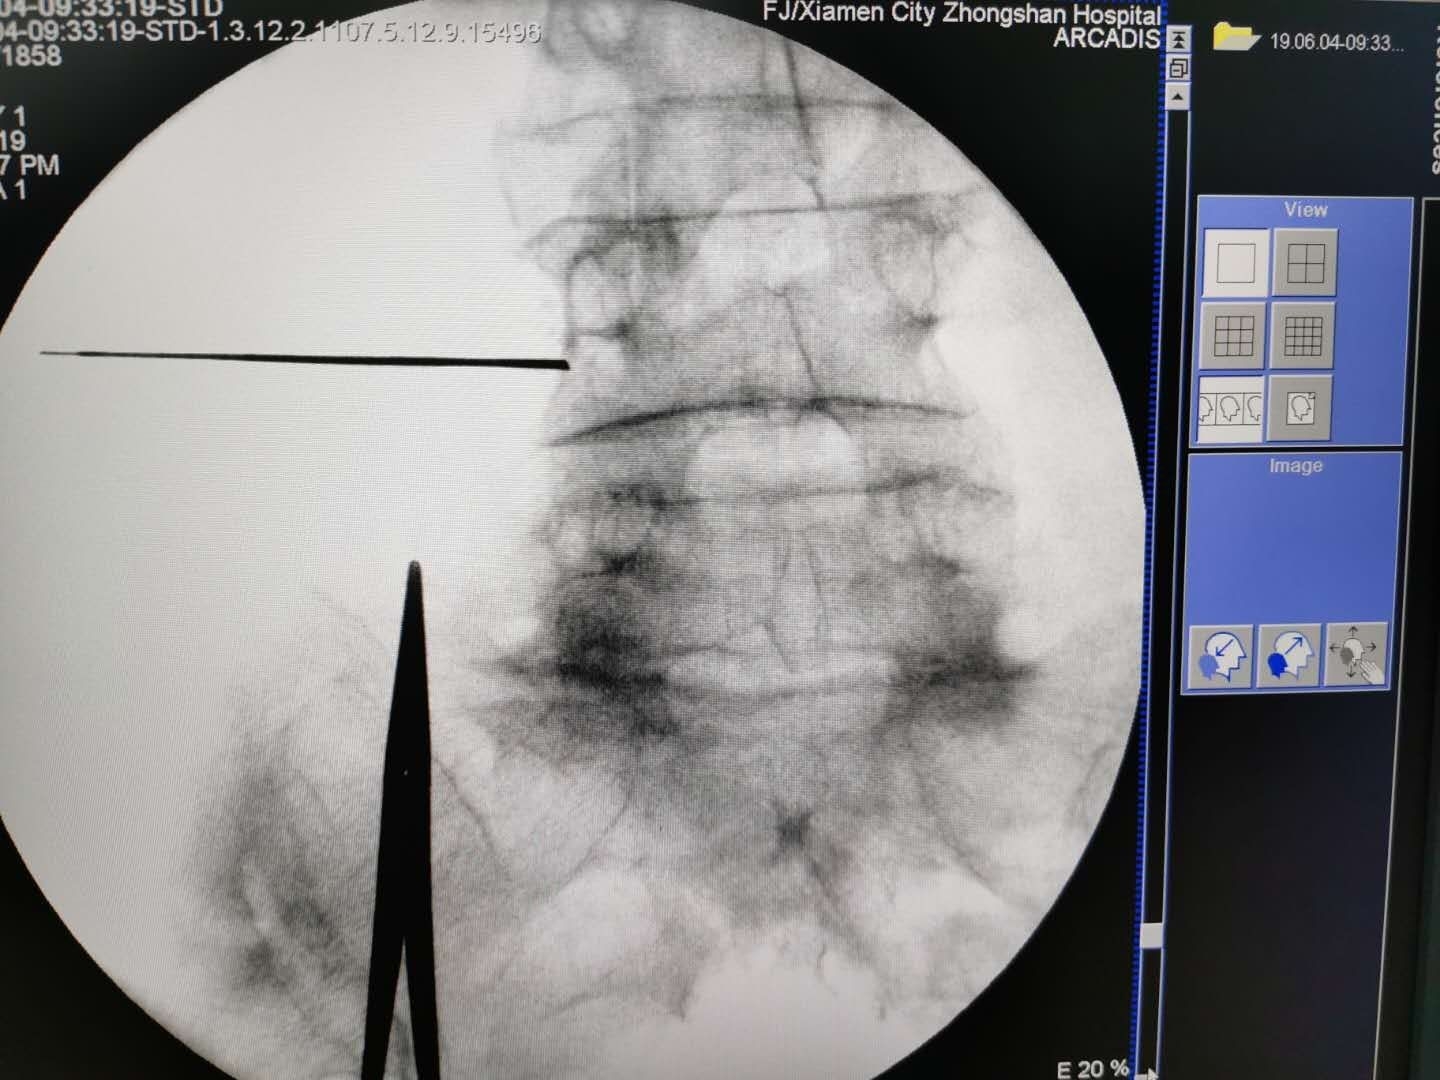

C臂透视左侧斜位片。腰4、腰5骶1左侧附件成苏格兰犬状。确定进针点。

在C臂辅助下穿刺针顺利到达目标靶点safety triangle

询问患者下肢没有异常。回抽证实处于安全区。遂注入药物。